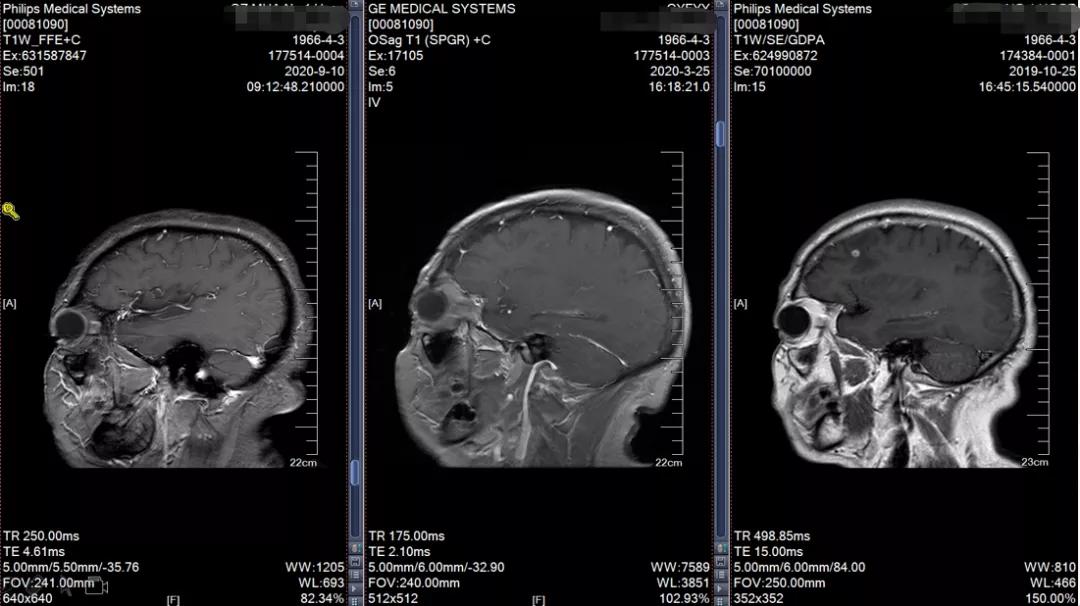

2019-10 头颅MRI示右额叶转移瘤,伴瘤旁水肿

2019-12-12头颅MRI示右侧额叶及左侧顶叶少许缺血灶,未见异常强化影

脑转移持续完全缓解